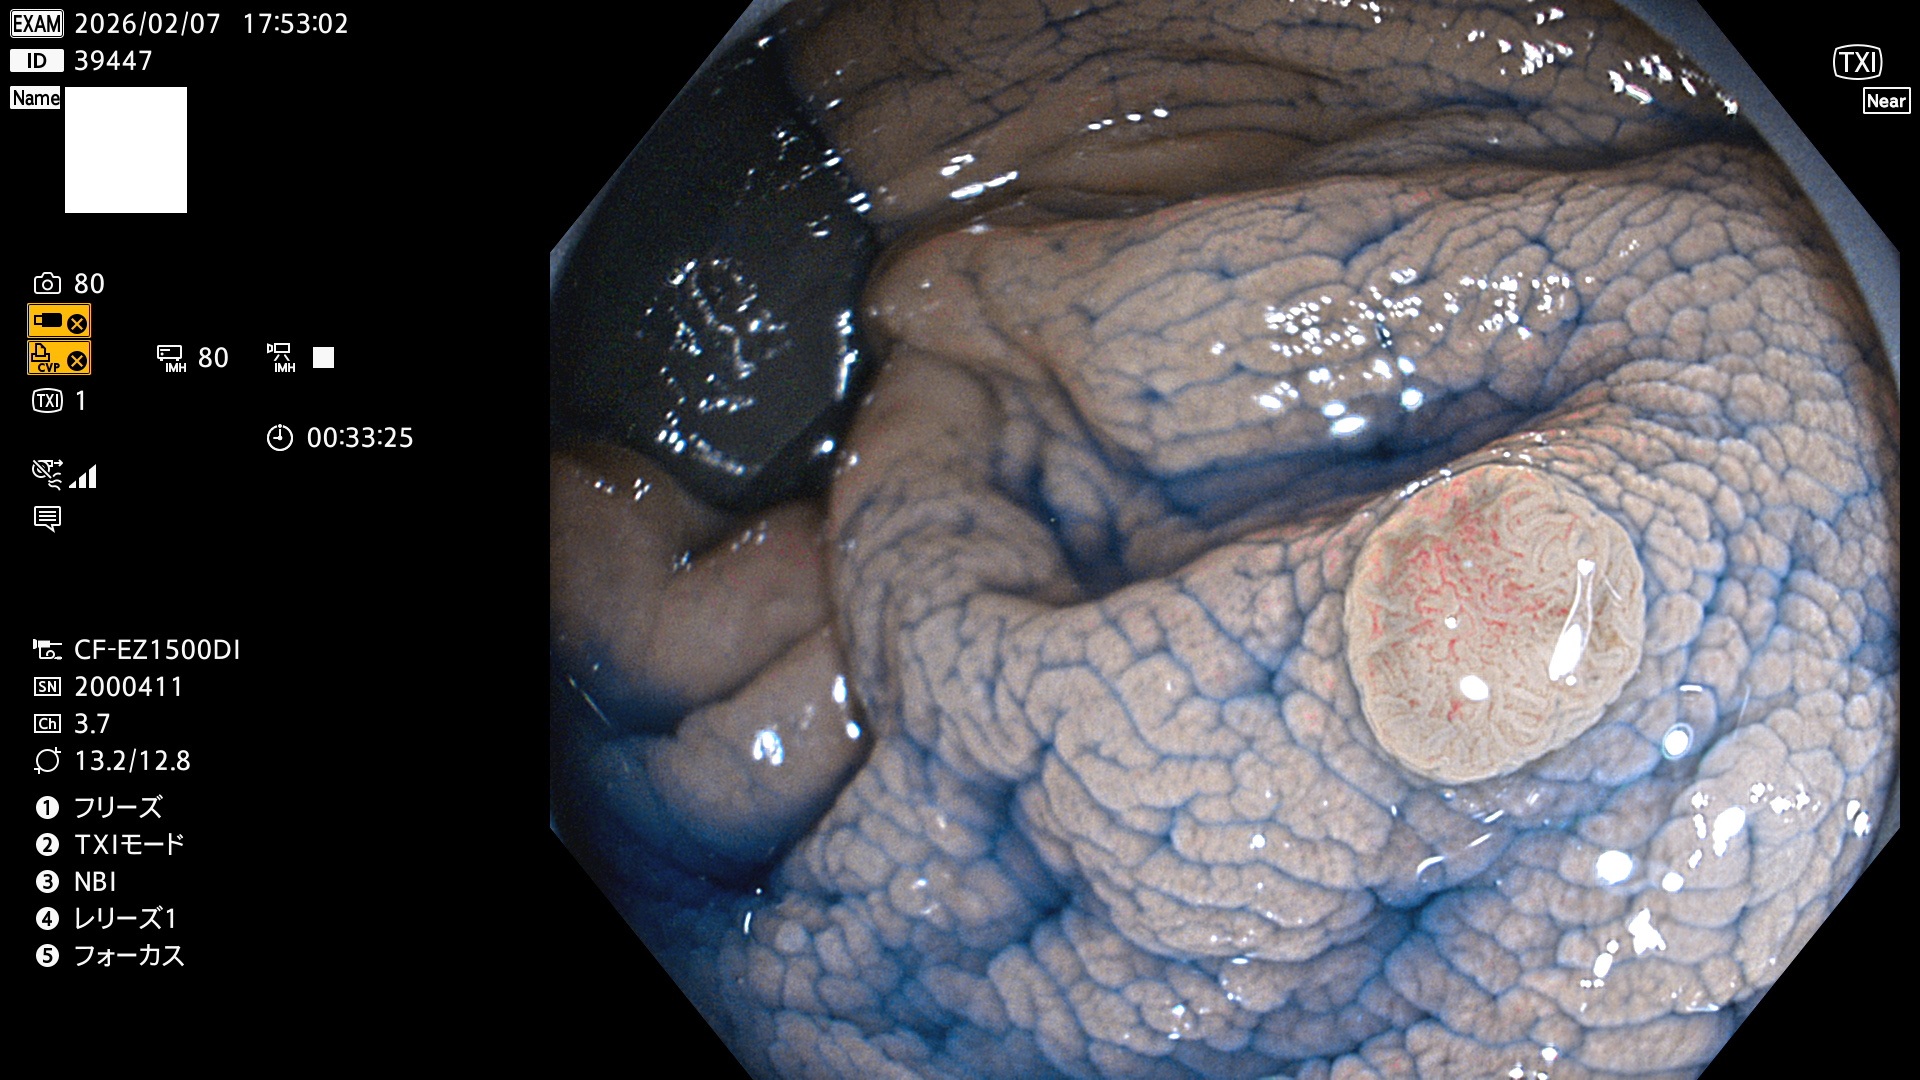

完全に平坦な物をUb、陥凹している物をUcと呼びます。Ubは認識が困難で、Ucはびらん(炎症)と紛らわしいために見落とされやすく、「内視鏡後・大腸癌」の原因になります。

専門的)Uc=De Novo癌? 内視鏡の解像度が低かった時代、このような説もありました。しかし今日の高精度内視鏡では良性の微小なUc型腺腫(APC遺伝子異常の腺腫)が日常的に見つかります。Ucこそが多段階発癌(Adenoma-Carcinoma Sequence)のMain Routeです。

毎週の検査(木・金・土・日)に発見されたUbとUc型・腺腫を、その週の日曜の夜にUPし1週間、提示します。

写真公開の目的は「透明性・信憑性の担保」ですが、公開を希望されない方はメールで御連絡下さい。直ちに削除いたします。

2026年2月5日〜2月8日の4日間(40件)9個 (Uc_ADR=9個/40人=23%)